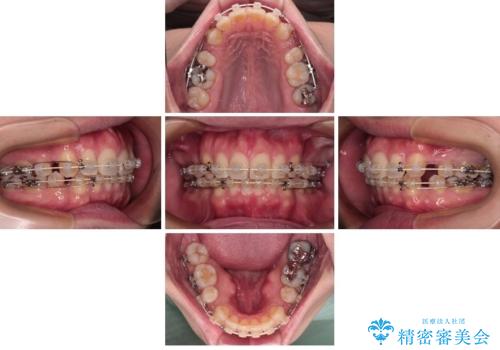

- 口元の突出感と下の前歯のがたつきを主訴として来院された患者様です。

口元の突出感と叢生改善のため上下左右の第一小臼歯4本を抜歯し、ワイヤー装置にて矯正治療を行うこととしました。

なるべく目立たない装置が希望だったため、審美装置で治療を行いました。

左上はアンカースクリューを併用することでスムーズに抜歯スペースを閉じることができました。

口元の突出感もなくなり満足されました。